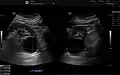

- Renal cyst as seen on abdominal ultrasound